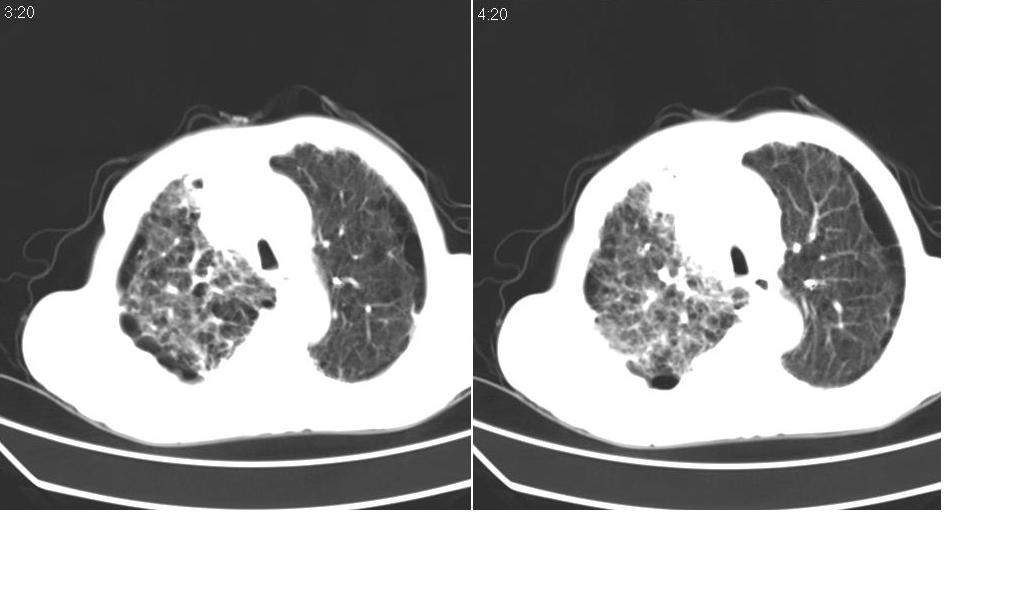

以下是引用zsl6918在2008-5-3 19:53:00的发言:[br]右肺中心型肺癌并纵隔淋巴结转移,胸膜转移,右肺癌性淋巴管炎。

以下是引用liuyue在2008-5-3 20:49:00的发言:[br]1.右侧中心型肺癌伴双肺转移瘤、纵隔淋巴结转移、右侧胸腔积液(侵及胸膜所致可能性大)。[br]2.右肺阻塞性肺炎,癌性淋巴管炎不除外。

以下是引用mzh123在2008-5-3 21:12:00的发言:[br]本人持有不同观点[br]1、右肺似有团块表现,但只有一个层面,所以本人认为还是以片为主,所以不能首先考虑肿瘤[br]2、右肺普遍成纤维化改变 并伴有片状炎症改变,和癌性淋巴管炎表现不同[br]3、所以本人认为是间质纤维化伴感染可能大 及胸腔积液